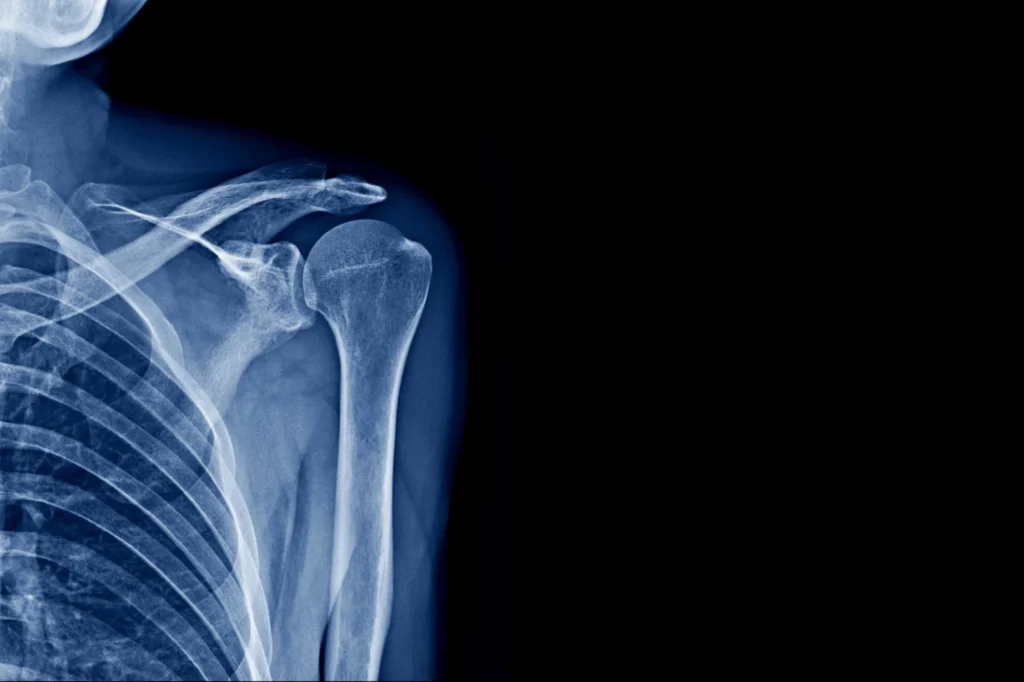

The shoulder is one of the most complex and mobile joints in the human body. This complexity, however, also makes it vulnerable to injury. A broken shoulder refers to a fracture in one of the three bones that make up the shoulder joint. These bones include the clavicle (collarbone), the scapula (shoulder blade), and the proximal humerus (the top part of the upper arm bone). Understanding the injury, the treatment options, and the recovery process is the first step toward healing.

To understand a broken shoulder, it helps to know the anatomy surrounding it. The shoulder is a ball-and-socket joint. The “ball” is the head of the humerus. The “socket” is the glenoid, a part of the scapula.

The three bones that may be involved in a shoulder fracture are:

- Clavicle (Collarbone): This long, slender bone connects the sternum (breastbone) to the shoulder blade. It acts as a strut to keep the shoulder in the correct position.

- Scapula (Shoulder Blade): This is a large, flat, triangular bone. It has several parts, including the glenoid (the socket), the acromion (the roof), and the coracoid process.

- Proximal Humerus: This is the top section of the upper arm bone. It includes the humeral head, which forms the ball of the joint.

Imaging supports the diagnosis and helps plan treatment. For a fracture, standard X-rays are typically the primary diagnostic tool. They provide clear images of the bone structure. Multiple views are taken to show the fracture pattern and displacement. A CT scan may be ordered for complex fractures. It provides a detailed, three-dimensional view of the bone fragments. This level of detail can be important for surgical planning.